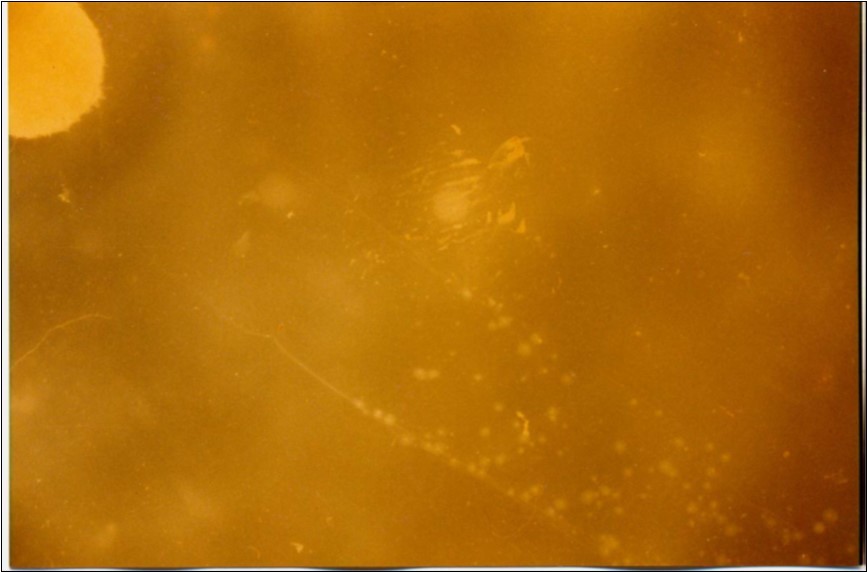

No mycoplasma was isolated from slaughterhouse samples. Three mycoplasma isolates were recovered from three out of six cases showing typical clinical signs and P.M. lesions. The isolates were identified as Mmm depending on cultural characteristics (Figure 1), digiton in test (Figure 2), and growth inhibition test.

Figure 1.Colonial morphology of Mmm of recent field isolate grown on heart infusion agar after 3 days of incubation (×40).